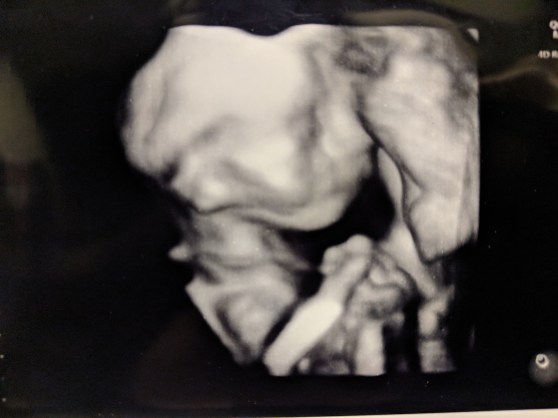

On Thursday, November First, Sofia and I went in for what was turning into a routine ultrasound. It was our eighth. After the diagnosis of Gastroschisis during Week 17, we had been under fairly intense observation. This ultrasound was being performed every two weeks. Our fridge was filling up with photos. Now at 28 weeks, we were starting to think that the constant ultrasounds were just a precaution.

But, as the technician started measuring our baby, it became apparent that this was not going to be normal. We’ve had very normal results all around–baby even had a big head like me. Overall, growth is in the 35th percentile or so. But, as the results of the ultrasound showed on the screen, a single result glared down on us. The abdomen was measuring in less than the first percentile. The line graph next to the number actual had us off to the left of the lowest expected result.

We were taken aback by this result. After all, Gastroschisis means that the intestines are not inside baby’s abdomen. That means the abdomen will not grow as fast. We had been told that. But this was unexpected. In the growth ultrasound from a month ago, the abdominal measurement was in the 45th percentile. In his growth ultrasound from two weeks ago, the abdomen was in the 25th percentile. It’s almost like baby’s abdomen was doing fine until a month ago and then…stopped.